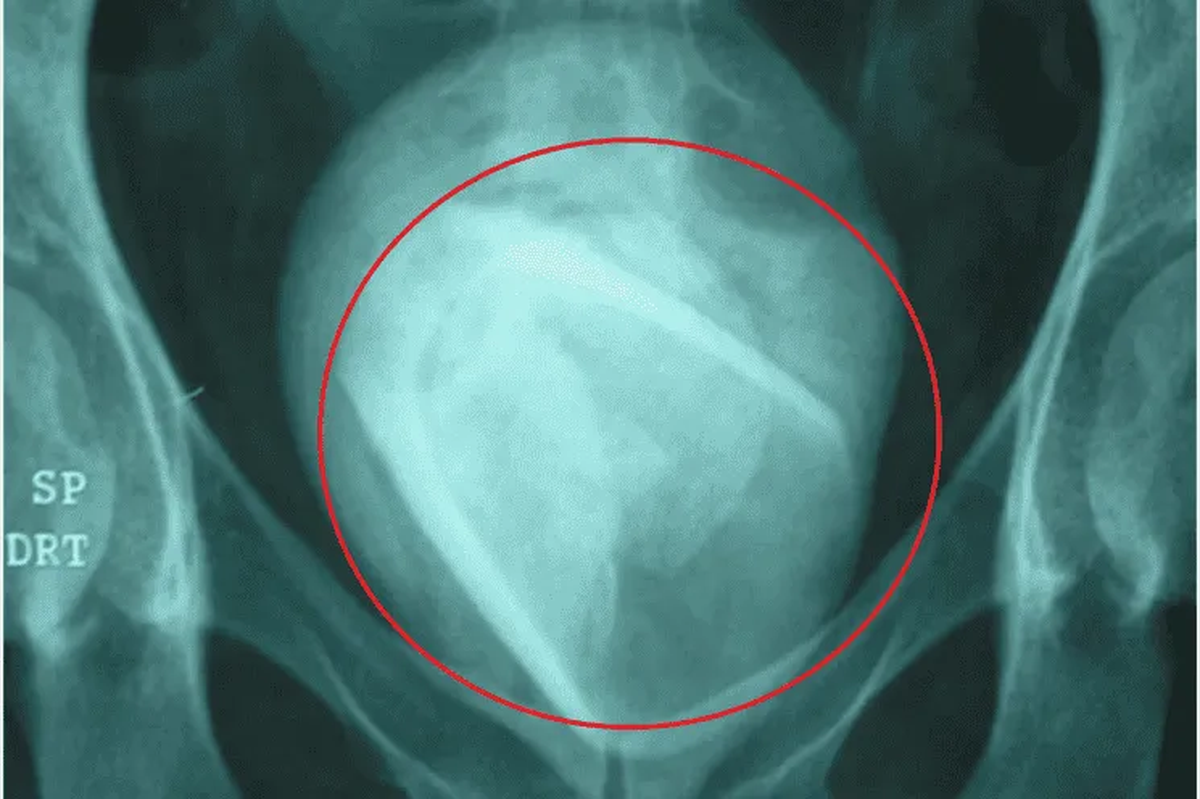

Esta semana, una mujer de 45 años llegó hasta el hospital de la ciudad de Sfax, Túnez, por un dolor fuerte en la zona vaginal. Ella ingresó diciendo que tenía una aguda infección urinaria, ya que tenía síntomas compatibles con dicha enfermedad. El médico que la atendió, la envió a realizarse diferentes estudios que incluyeron laboratorio, ecografías y ultrasonidos. Los resultados obtenidos de la prueba no fueron los esperados. El equipo de doctores del Centro Clínico Académico Habib Bourguiba descubrió que la paciente tenía un vaso de vidrio dentro de su vejiga. Como si fuera poco, el objeto cortante estaba encerrado dentro de un cálculo vesical de 8 centímetros de ancho.

Según informa el sitio web Crónica, tras el diagnóstico, la mujer confesó que utilizó el vaso en una práctica sexual. Se lo había introducido en la uretra y sin darse cuenta lo dejó en su cuerpo. La sorpresa llegó cuando aseguró que el elemento estuvo en su organismo al menos cuatro años. El estado de la paciente era crítico, por lo que los especialistas tuvieron que intervenir quirúrgicamente. La operación era la única forma de quitar el objeto de esa zona tan delicada, en caso contrario la señora tenía riesgo de muerte por la rotura del cálculo vesical.